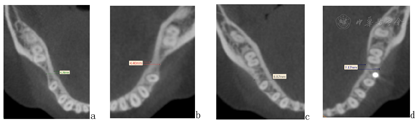

曲面断层片:36、46缺失,37、47近中倾斜,16、24、26、34、37、47充填体影像;上下颌前牙区牙槽骨萎缩至根中1/3,双侧升支长度、髁突大小形态基本对称。头影测量片:骨性I类均角,上前牙唇倾、下前牙舌倾(图1),具体结果见表1。锥形束CT冠状位下颌第二磨牙釉牙骨质界高度截图显示:下颌第一磨牙缺隙处牙槽嵴狭窄,牙槽骨颊舌向厚度右侧为4.78 mm,左侧为4.40 mm(图7a、b)。

覆盖正常,中线对齐,双侧尖牙中性关系、磨牙完全远中关系,尖窝交错,缺牙间隙关闭未见明显龈退缩。曲断片37、38、47、48得到直立牙根平行较好,未发现明显的牙根吸收和齿槽嵴骨吸收的情况。临床检查下前牙区有少量龈退缩及牙龈黑三角情况(图5)。保持期追踪显示牙齿咬合排列保持良好拥挤间隙未见复发,缺牙间隙闭合紧密,面型良好(图6)。治疗前后的锥形束CT对比显示,植骨区域牙槽骨宽度有显著增加,移入缺隙内的下颌第二磨牙及第二前磨牙未见骨开窗骨开裂(图7)。

患者双侧下颌第一磨牙的缺牙间隙由于缺牙时间很长已经发展为刃状,在将第二磨牙直立前移的过程中可能会出现骨开窗骨开裂等问题。虽然有研究报道称在正畸直接关闭萎缩缺牙间隙的过程中由于建牙合咬合力的传导牙槽骨改建牙槽嵴宽度和高度有不同程度的增加[9],但也可能是牙齿移出牙槽骨外导致其宽度增加[10]。并且患者年龄较大,相对于年轻成人或青少年患者,其骨改建能力更弱。为此我们在移动下颌牙列前为患者进行了缺隙处水平骨增量手术,预备下颌第二磨牙的前移空间,避免可能出现的骨开窗骨开裂问题。手术过程中的骨皮质打孔过程也有类似于皮质骨切开手术的局部加速现象(regional acceleratory phenomenon, RAP),激发了局部成骨细胞和破骨细胞活性,炎性因子水平升高,提高了骨改建速度[11]。这种现象在皮质骨损伤后几天就可发生,1~2个月达到顶峰,效应持续6个月[12]。关于术后多久开始正畸加力移动临床上一直没有明确的指南规范,Mayer等[6]建议术后6个月再开始将牙齿移入萎缩的牙槽嵴,但这也丧失了利用RAP加快牙齿移动的机会;有临床报道最早术后两周开始牙齿移动,以便充分利用RAP加速牙齿移动效果[13]。本例患者在术后6周开始下颌牙列的矫治和间隙关闭,在充分保障骨移植材料愈合稳定性的基础上提高牙齿移动效率。

研究表明相比于缺牙间隙的长度,治疗前缺牙区的牙槽骨宽度和高度对间隙关闭后的牙周状况影响更大[14],Wu等[3]成功关闭一例缺牙间隙牙槽骨宽度<7 mm的患者,但是间隙关闭后近中前移磨牙颊舌侧牙龈明显退缩。可见确保在骨松质内安全移动的前提是缺牙区牙槽骨宽度大于7mm,必要时也可在缺牙区进行骨增量手术[15]。本例患者颊舌侧牙槽骨缩窄呈Ⅲ度(Cawood&Howell分类法),为了能更好创造牙槽骨颊舌向宽度利于磨牙近中移动,在手术方式上区别于常规的牙周加速成骨正畸手术(periodontally accelerated osteogenic orthodontics, PAOO),我们采用了"帐篷法"水平骨增量手术的方式[16],通过植入钛钉和覆盖生物膜的方式,更好的固定骨粉材料和获得水平向骨增量,最终患者在间隙关闭后未见明显的牙龈萎缩,其牙槽骨高度没有进一步降低,且植骨带来的牙槽骨宽度增加也保持稳定。相较于夹层植骨方式(三明治法),本例患者由于受倾斜牙齿的影响缺隙近远中间距相对较小,帐篷法手术入路更加便捷,且避免了严重萎缩下颌牙槽骨在手术过程中的骨折和神经损伤的风险[17];同时打通了骨皮质,有效利用了区域增速效应,在保证骨宽度的同时更增加了牙齿的移动。